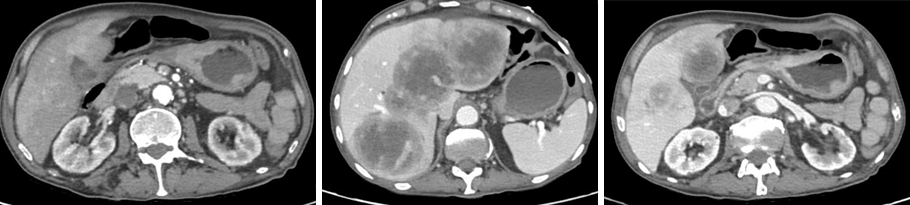

Dans ce contexte, vous lui organisez une gastroscopie rapidement et vous lui prescrivez un scanner thoraco-abdomino-pelvien dont voici les images.

Figure 3 (Élisabeth Capelle, La Revue du Praticien)

Question 7 - Sur le scanner, vous observez (une ou plusieurs réponses exactes) :

Il n’y a pas de dilatation du tube digestif, ni de jonction grêle plat-grêle dilaté.

On voit des métastases hépatiques mais le foie n’est pas à contours bosselés.

On voit une masse tissulaire qui fait saillie de la paroi (voir figure 4).

Il n’y a pas de liquide libre dans la cavité péritonéale.

La rate se rehausse bien, sans hypodensité.

Figure 4 (Élisabeth Capelle, La Revue du Praticien)

Dans le carré rouge : masse gastrique suspecte.

Étoiles bleues : métastases hépatiques.

Triangle vert : rate d’aspect normal.